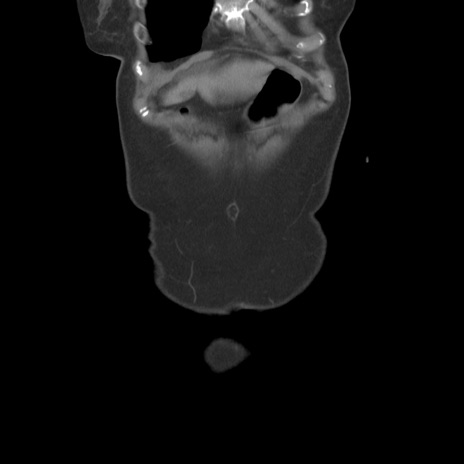

横断像

【症例】80歳代女性

【主訴】下腹部痛

【現病歴】約8時間前より下腹部痛の出現あり、救急外来受診。

【既往歴】両側付属器切除

【身体所見】意識清明、下腹部正中に手術痕あり、その部位に一致して圧痛と反跳痛あり。腸蠕動音は亢進。

【データ】WBC 9300、CRP 0.15